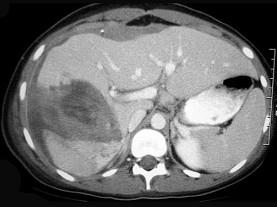

问题 处理肝外伤哪一项是不正确的 ( )

选项 A、肝创面处要放置引流 B、严重广泛的肝组织损伤可行肝叶或肝部分切除 C、压动肝动脉有止血效果的可结扎肝动脉 D、失去活力的肝组织应予清除或切除 E、裂痕稍大的可用纱布填塞

答案 E